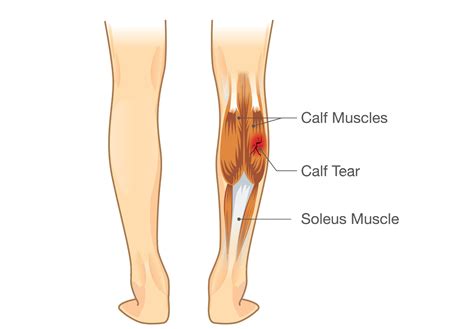

A tear in calf, also known as a calf strain, occurs when the muscles in the back of the lower leg are overstretched or torn. The calf muscles, which include the gastrocnemius and soleus, are essential for activities like walking, running, and jumping. A tear in calf can range from mild to severe, depending on the extent of the damage.